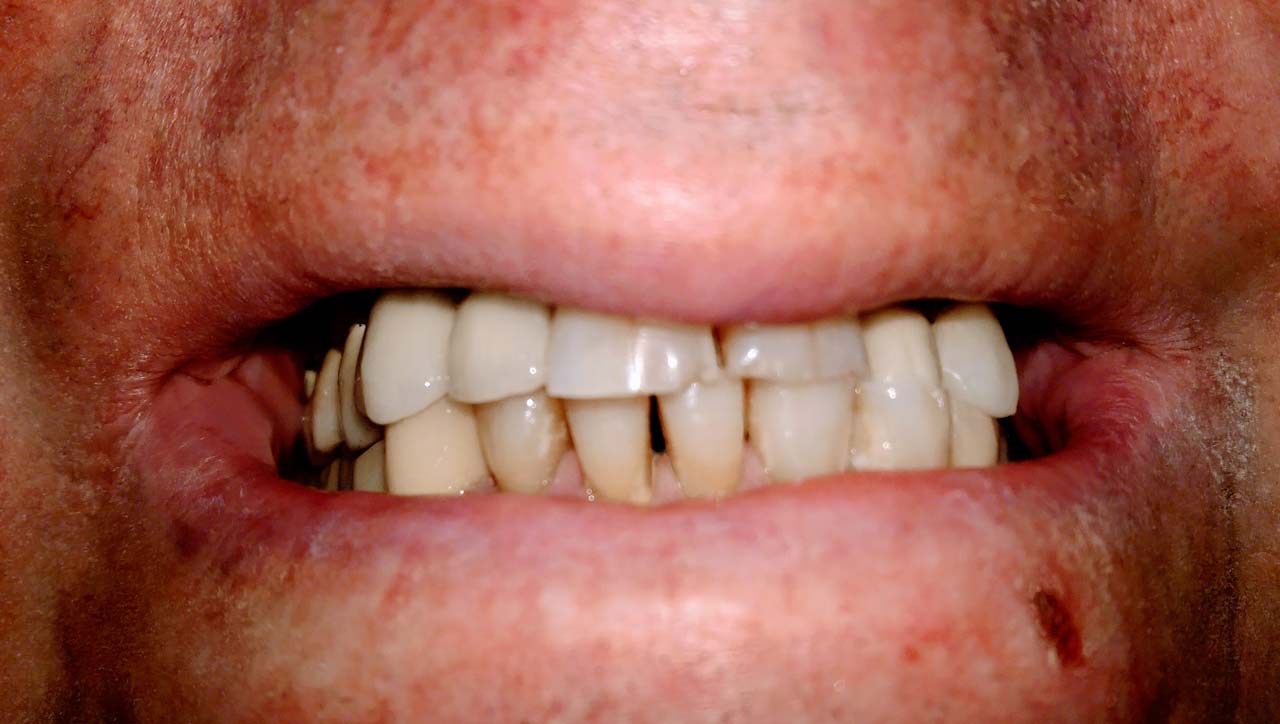

Teljes alsó,felső állcsont helyreállítása azonnal

terhelhető implantátumokkal és porcelán hidakkal.